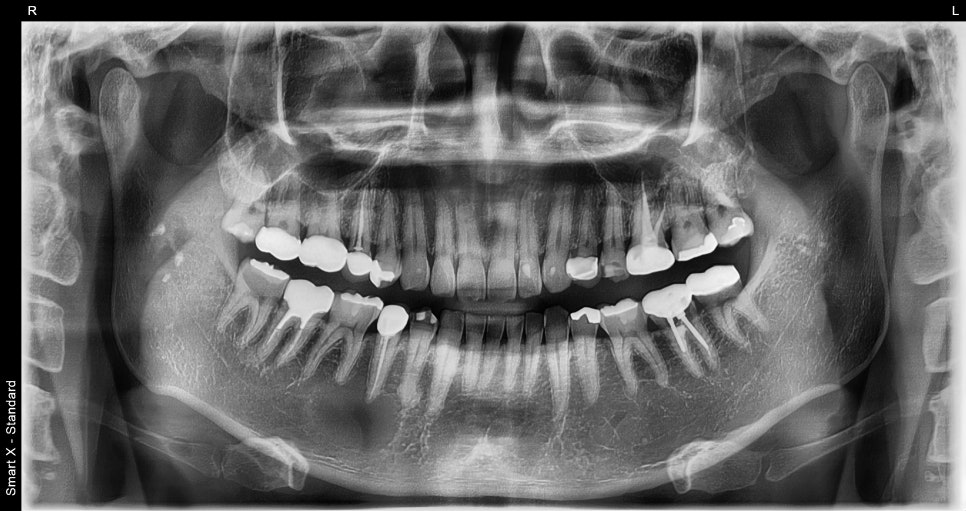

파노라마 촬영 및 CBCT(3D CT) 검사 결과,

해당 부위 하악골 내에 경계가 명확한 방사선 투과성 병소가 확인되었습니다.

📸 수술 전

– 치근단 부위에 낭종성 병소